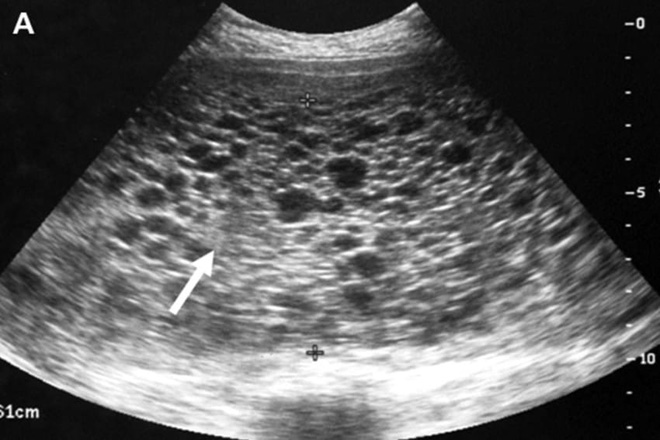

Nhìn vào hình ảnh siêu âm, bụng của người vợ không có phôi thai mà chỉ là những khối u nhỏ chi chít y hệt một chùm nho. Đây là một hiện tượng hiếm gặp, gọi là thai trứng.

Kết quả siêu âm cho thấy trong bụng cô toàn những túi nhỏ chi chít như chùm nho (Ảnh: Internet)

Thai trứng là do sự phát triển bất thường lớp tế bào nuôi có trong gai nhau. Bình thường, sau khi tinh trùng kết hợp với noãn sẽ trở thành trứng thụ tinh, phát triển thành thai nhi và các phần phụ như nhau và túi ối. Trong một số trường hợp, tế bào nuôi phát triển quá nhanh, tổ chức liên kết và các mao mạch của mạch máu rốn ở gai nhau không phát triển kịp. Gai nhau bị thoái hóa, phù nề tạo thành các túi chứa dịch dính vào nhau giống như chùm nho và chiếm phần lớn buồng tử cung. Tình trạng thai trứng đa số là lành tính, tuy nhiên cũng có khoảng 10% trường hợp có thể phát triển thành biến chứng ác tính như thai trứng xâm lấn hay ung thư nhau thai.